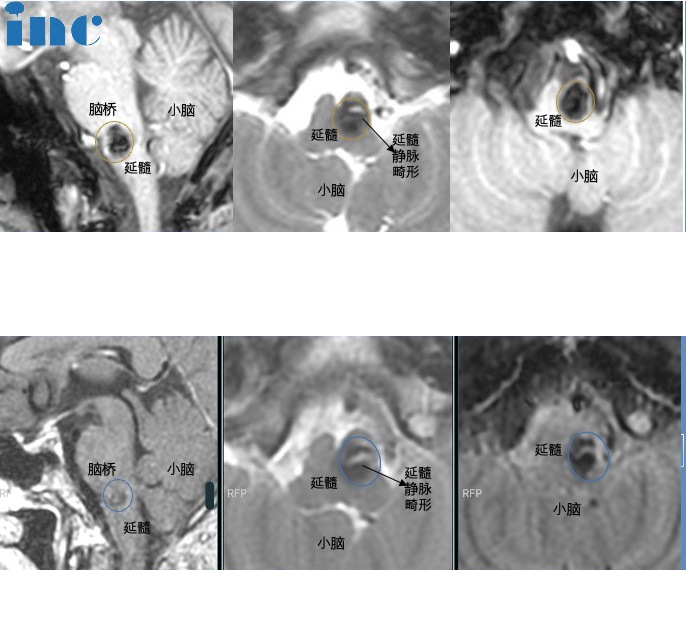

32岁男性-脑干延髓海绵状血管瘤

患者情况:一年前,三十多岁正处于事业上升期的冯先生因为偶发的手麻就医检查,未曾想到这一查竟是可怕的脑干海绵状血管瘤,且位置位于及其凶险的延髓部位,延髓作为人体的生命中枢,掌管着呼吸、心跳等重要的功能,一旦延髓海绵状血管瘤引发严重出血,可能会导致瘫痪、呼吸障碍等严重后果。“整整一年晚上睡不好,半夜睡梦中惊醒都会不时恍惚,一向身体不错的自己竟然在生命中枢的位置长了一颗‘不定时炸弹’,医生都不建议手术,建议伽马刀治疗”。冯先生不甘心年轻的自己就这样整日受到病魔的威胁。

治疗过程:2022示范手术中成功手术,“没有任何不舒服”,冯先生怎么也想不到困扰自己一年,让自己吃不好睡不好的“脑干肿瘤”就这样顺利全切了,且无新发功能损伤。

术后情况:术后一天,巴教授查房时,冯先生状态良好,“没有不舒服的地方”,巴教授查看了冯先生情况后,也对冯先生说“可以下地来走走,没问题的”。术后两个月,冯先生已经完全恢复了正常的生活,和家人一起回归到健康安稳的幸福生活之中。

21岁男孩-脑干海绵状血管瘤

简要病史:21岁的大男孩阿豪2年前在学校他却突然感觉站不稳想吐,之后持续数日的头晕、乏力、睡眠质量下降呕吐,让阿豪警惕起来,观察后不见好转的他来到医院进行检查,没想到检查结果果然异常,头部CT显示延髓后方近小脑见大小约6.8*9.9mm的片状高密度阴影,怀疑脑干海绵状血管瘤。面对面直接线下咨询巴教授,巴教授表示脑干海绵状血管瘤需要手术,自己可以全切。

治疗过程:3月29日,在苏州独墅湖医院,巴教授顺利为阿豪全切脑干海绵状血管瘤。

术后情况:术后1天巴教授ICU查房,阿豪意识清醒、对答如流,吞咽、舌头活动、头部活动等情况,术后9天,阿豪恢复良好,行走自如。术后两周,阿豪恢复很好,无新发症状,阿豪现在已经顺利出院。术后两个月恢复正常生活。